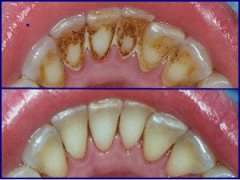

tartarectomia

O tratamento é realizado em função da gravidade e estado das lesões tendo como objectivo eliminar o tártaro e as bactérias nele presentes.

Nos casos mais simples, gengivites, a tartarectomia (vulgo "limpeza") seguida de uma melhoria da higiene são suficientes. Nos casos mais avançados, periodontites, é necessário raspar o tártaro das raízes afectadas e ocasionalmente recorrer a cirurgias periodontais.